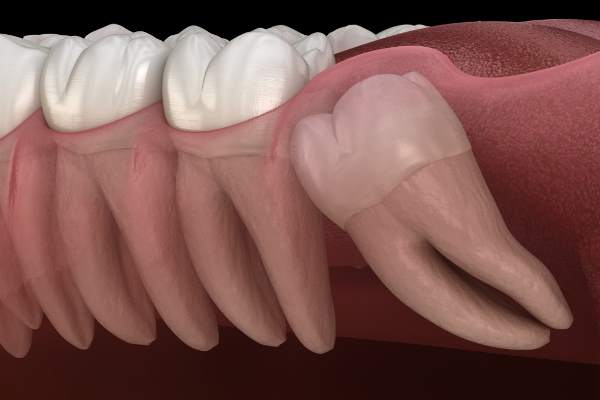

The dental cysts are cavities, lined with a movie of lining epithelial tissue, which seem inside a tooth and fill with fluid, inflicting irritation, in some circumstances even to the encircling tissues.

A dental cyst it’s outlined as such when it’s lined with a epithelial tissue movie, that may be a skinny layer of compact cells that has the perform of a “bag”, and when it is stuffed with fluid, serous, mucous or gaseous. If in case you have a cyst with out an exterior capsule, converse of pseudocysts, whereas in case the liner is stuffed with pus (contaminated blood), it involves dental abscesses.

- Radicular– is the most typical sort of cyst that develops on account of infections of the inner tissues of the tooth. On this case, explicit consideration should be paid, as a result of being inner to the dental construction it could possibly enlarge till it breaks the bone.

Among the many triggering causes that may result in the formation of dental cysts, there are additionally operations and coverings within the mouth with problematic programs, specifically, equivalent to poorly handled dental inclusions, dangerous tooth extractions and issues following devitalization operations.

The earlier a cyst is handled, the higher: as talked about, their progress can lead as much as rupture of the alveolar bone the place the tooth is inserted, and likewise transfer the tooth by pushing them collectively, thus modifying the construction of the dental equipment and inflicting different associated issues.

- With a surgical procedure which is carried out underneath native anesthesia. The operation includes the incision of the gum, the potential elimination of the bone protecting the cyst, and the elimination of the epithelium and the contents of the cyst itself.